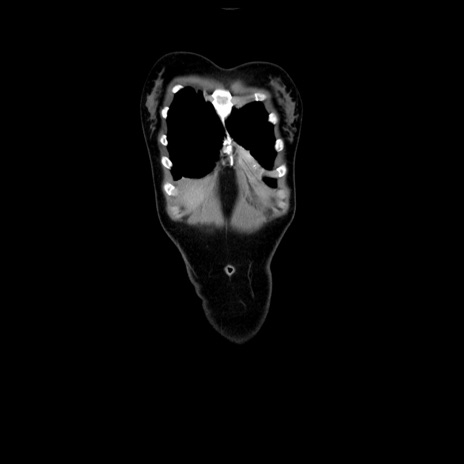

症例39(冠状断像)

CT